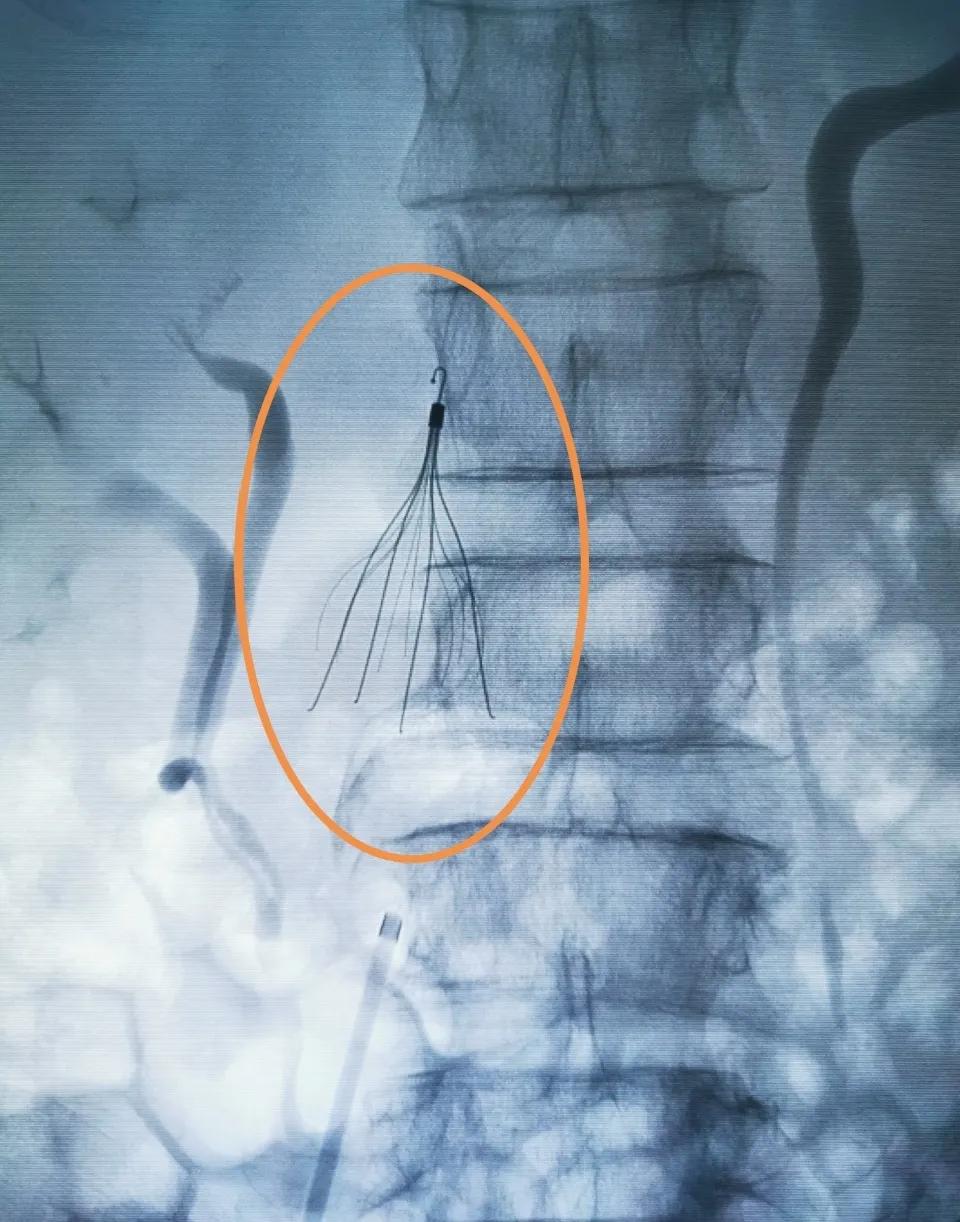

老年男性患者外伤入院,诊断右股骨粗隆间骨折。右下肢深静脉超声检查提示:右股静脉血栓形成。

为预防骨科手术术中静脉血栓脱落致肺栓塞,骨科邀请了介入科主任赵旭辉为患者行下腔静脉滤器置入。

右图圆圈内为经股静脉穿刺置入下腔静脉滤器。

术中造影示腔静脉通畅,无静脉血栓附壁。

下腔静脉滤器置入术创伤小,可回收性好,既能截获栓子,又能保持下腔静脉的通畅。有效防止了肺栓塞的发生,并大大的降低了并发症的发生。该手术的成功开展,标志着莆田涵江医院外周介入手术取得了新的突破。